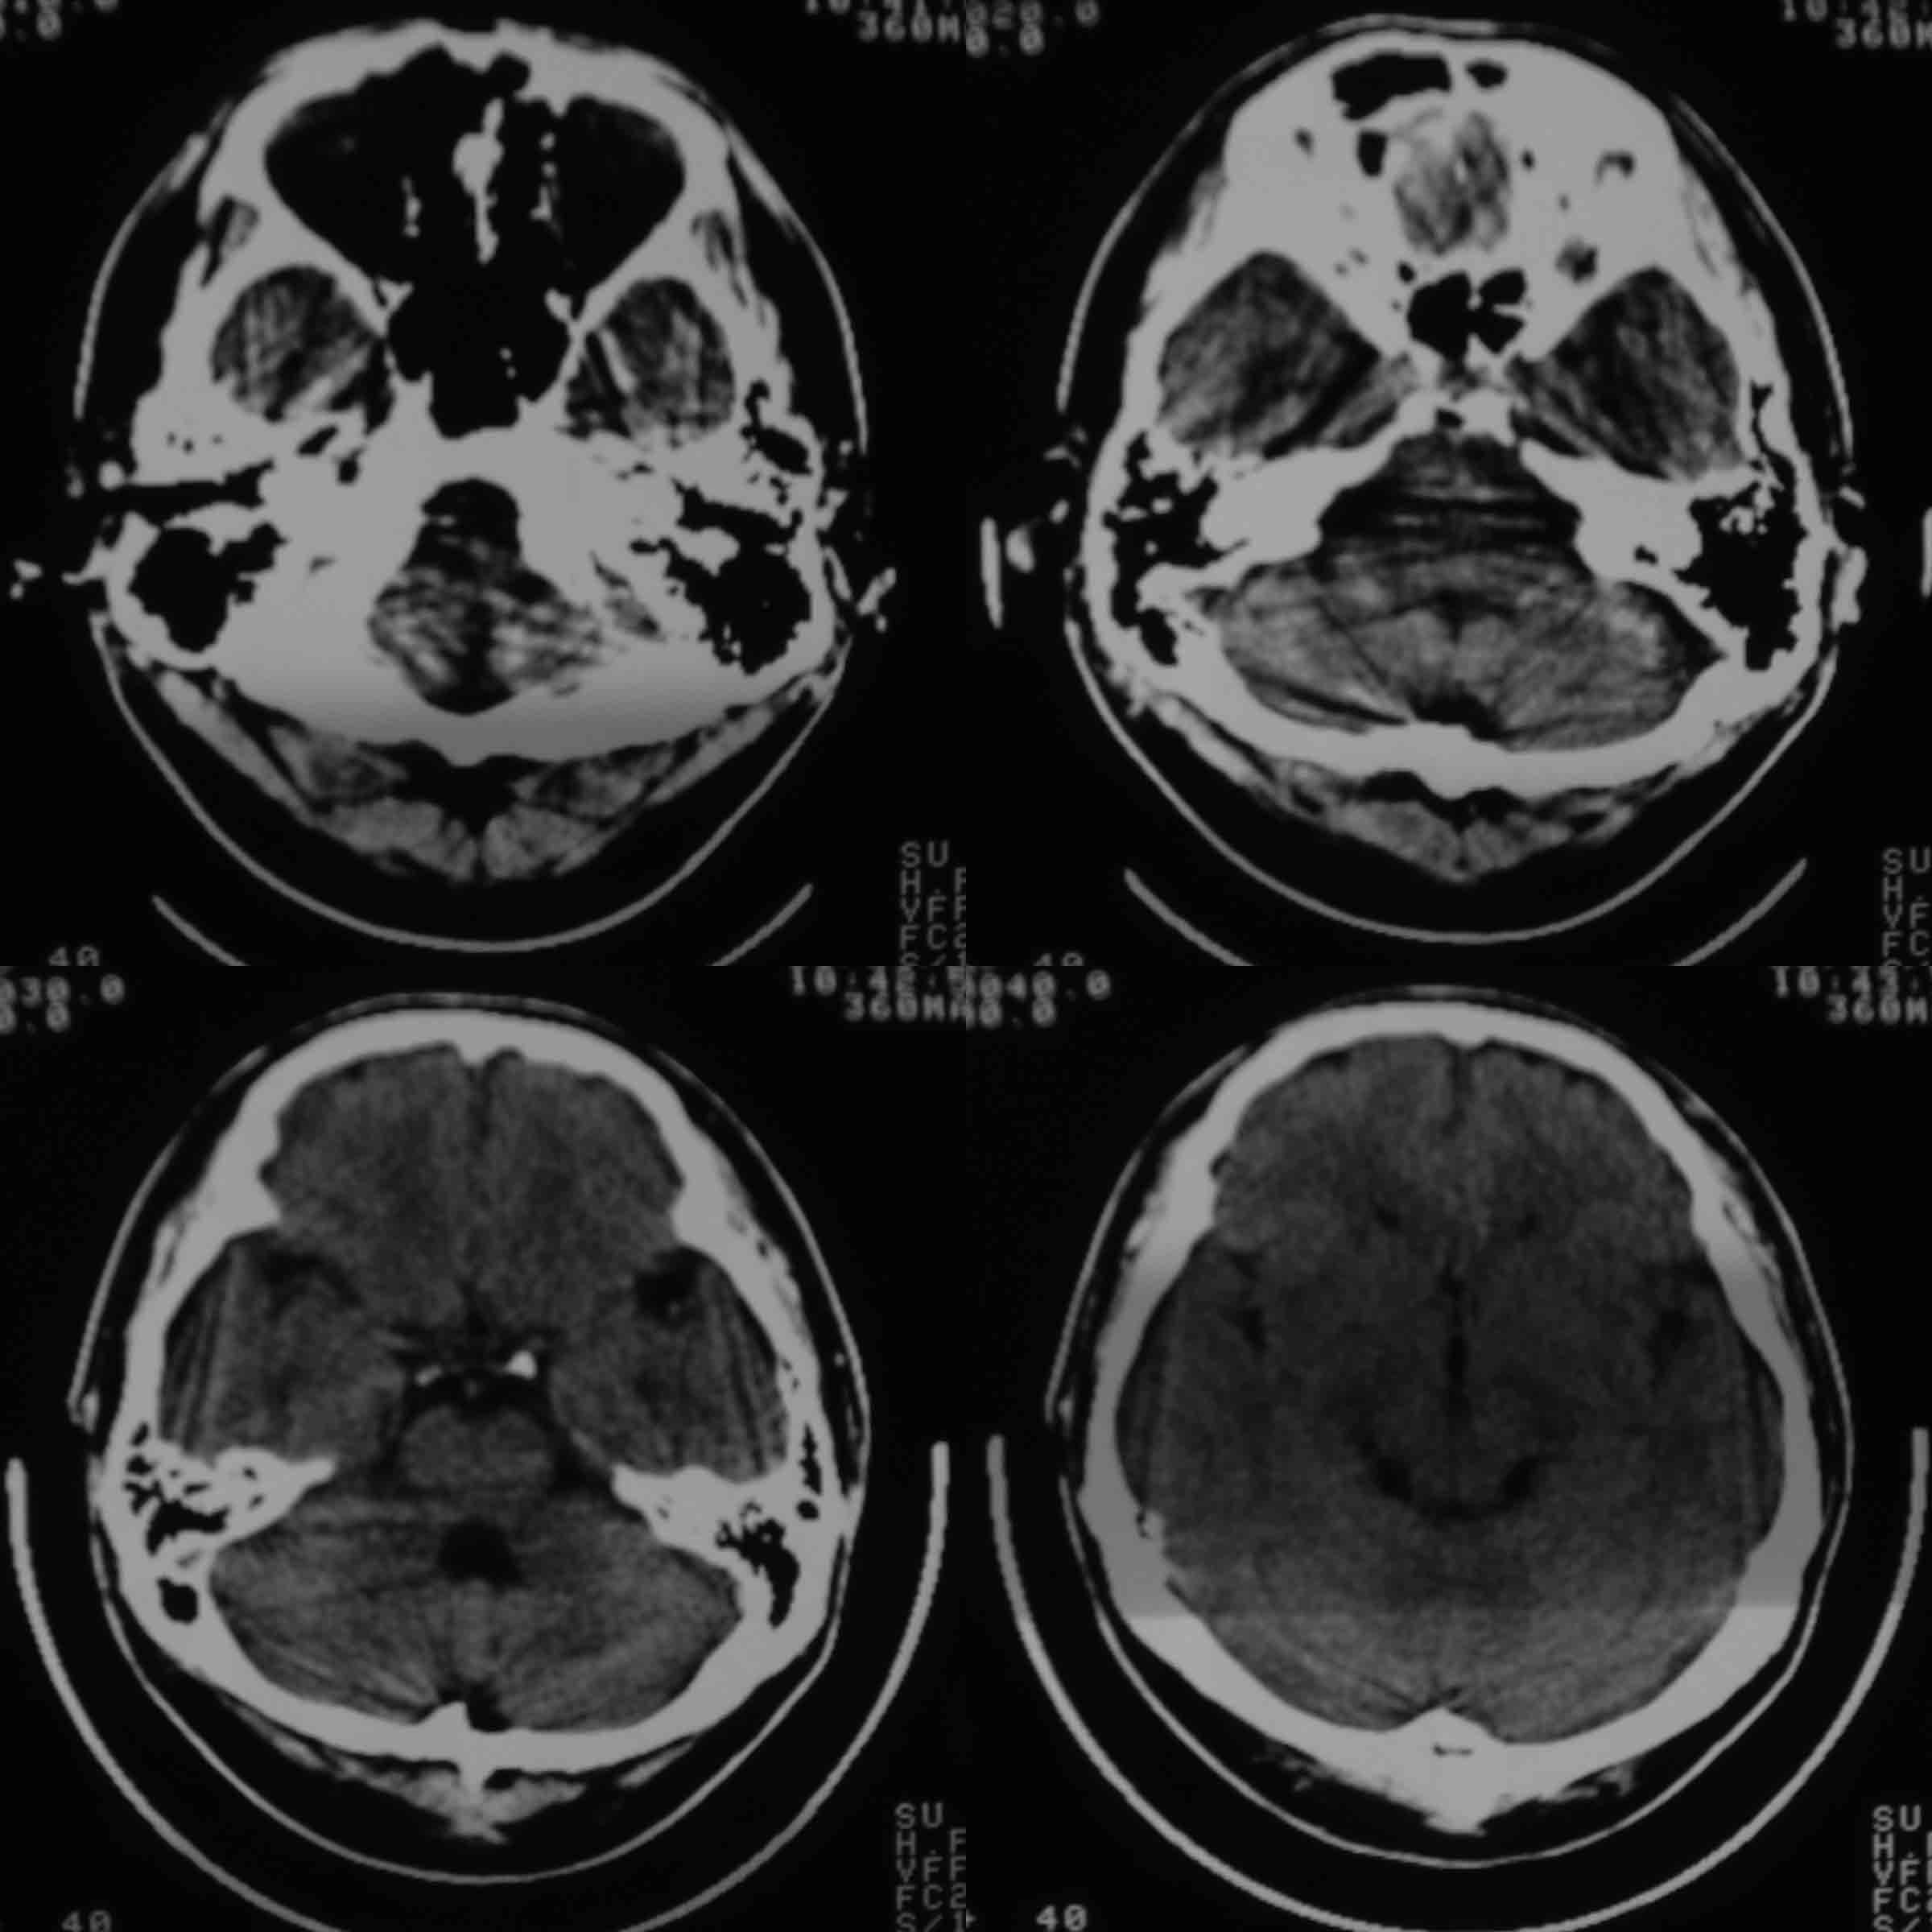

男37岁头持续性痛1天。右额部蛛网膜下腔囊肿诊断是否正确,请老师们帮忙看看。谢谢!

支持右额区蛛网膜囊肿。

有顶叶蛛网膜下腔囊肿

右侧额叶蛛网膜囊肿。